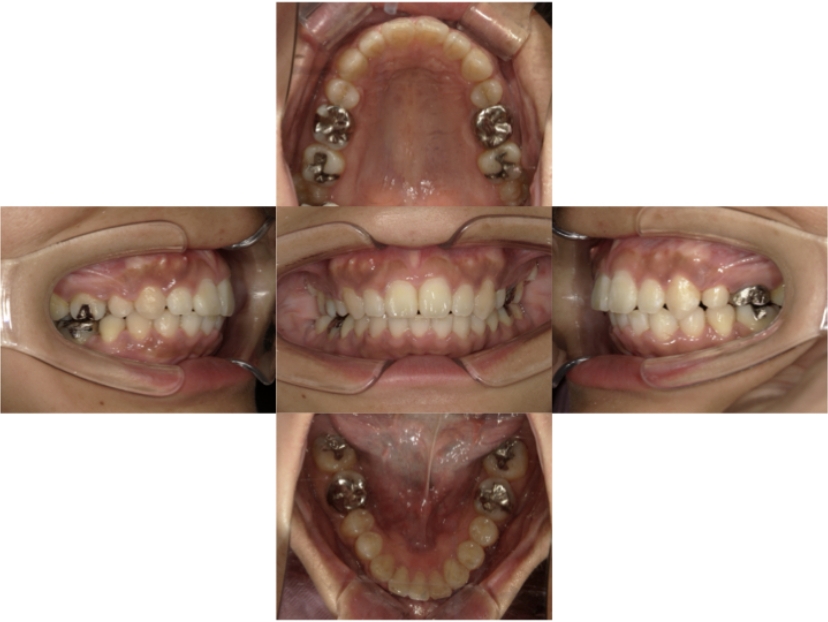

症例4

下顎前突、叢生

抜歯

ブラケット矯正

上下顎叢生、反対咬合(上下の前歯のガタガタ、若干受け口)のケースです。

装置はラビアル(上下表側)で、上下顎の小臼歯を4本抜歯を行っています。抜歯したスペースを使って、上下の叢生改善と前歯の受け口の改善を行っています。

主訴 前歯のガタガタを治したい。

年齢・性別 45歳 女性

お住まいの地域 神奈川県川崎市

治療方針 抜歯スペースを利用して上前歯の叢生(ガタガタ)の改善と受け口の改善

抜歯部位 上顎左右第一小臼歯、下顎左右第二小臼歯

使用装置 ラビアル(上下表側)、顎間ゴム

治療期間 2年6か月

治療回数 20回

リテーナー クリアリテーナー

BEFORE

AFTER